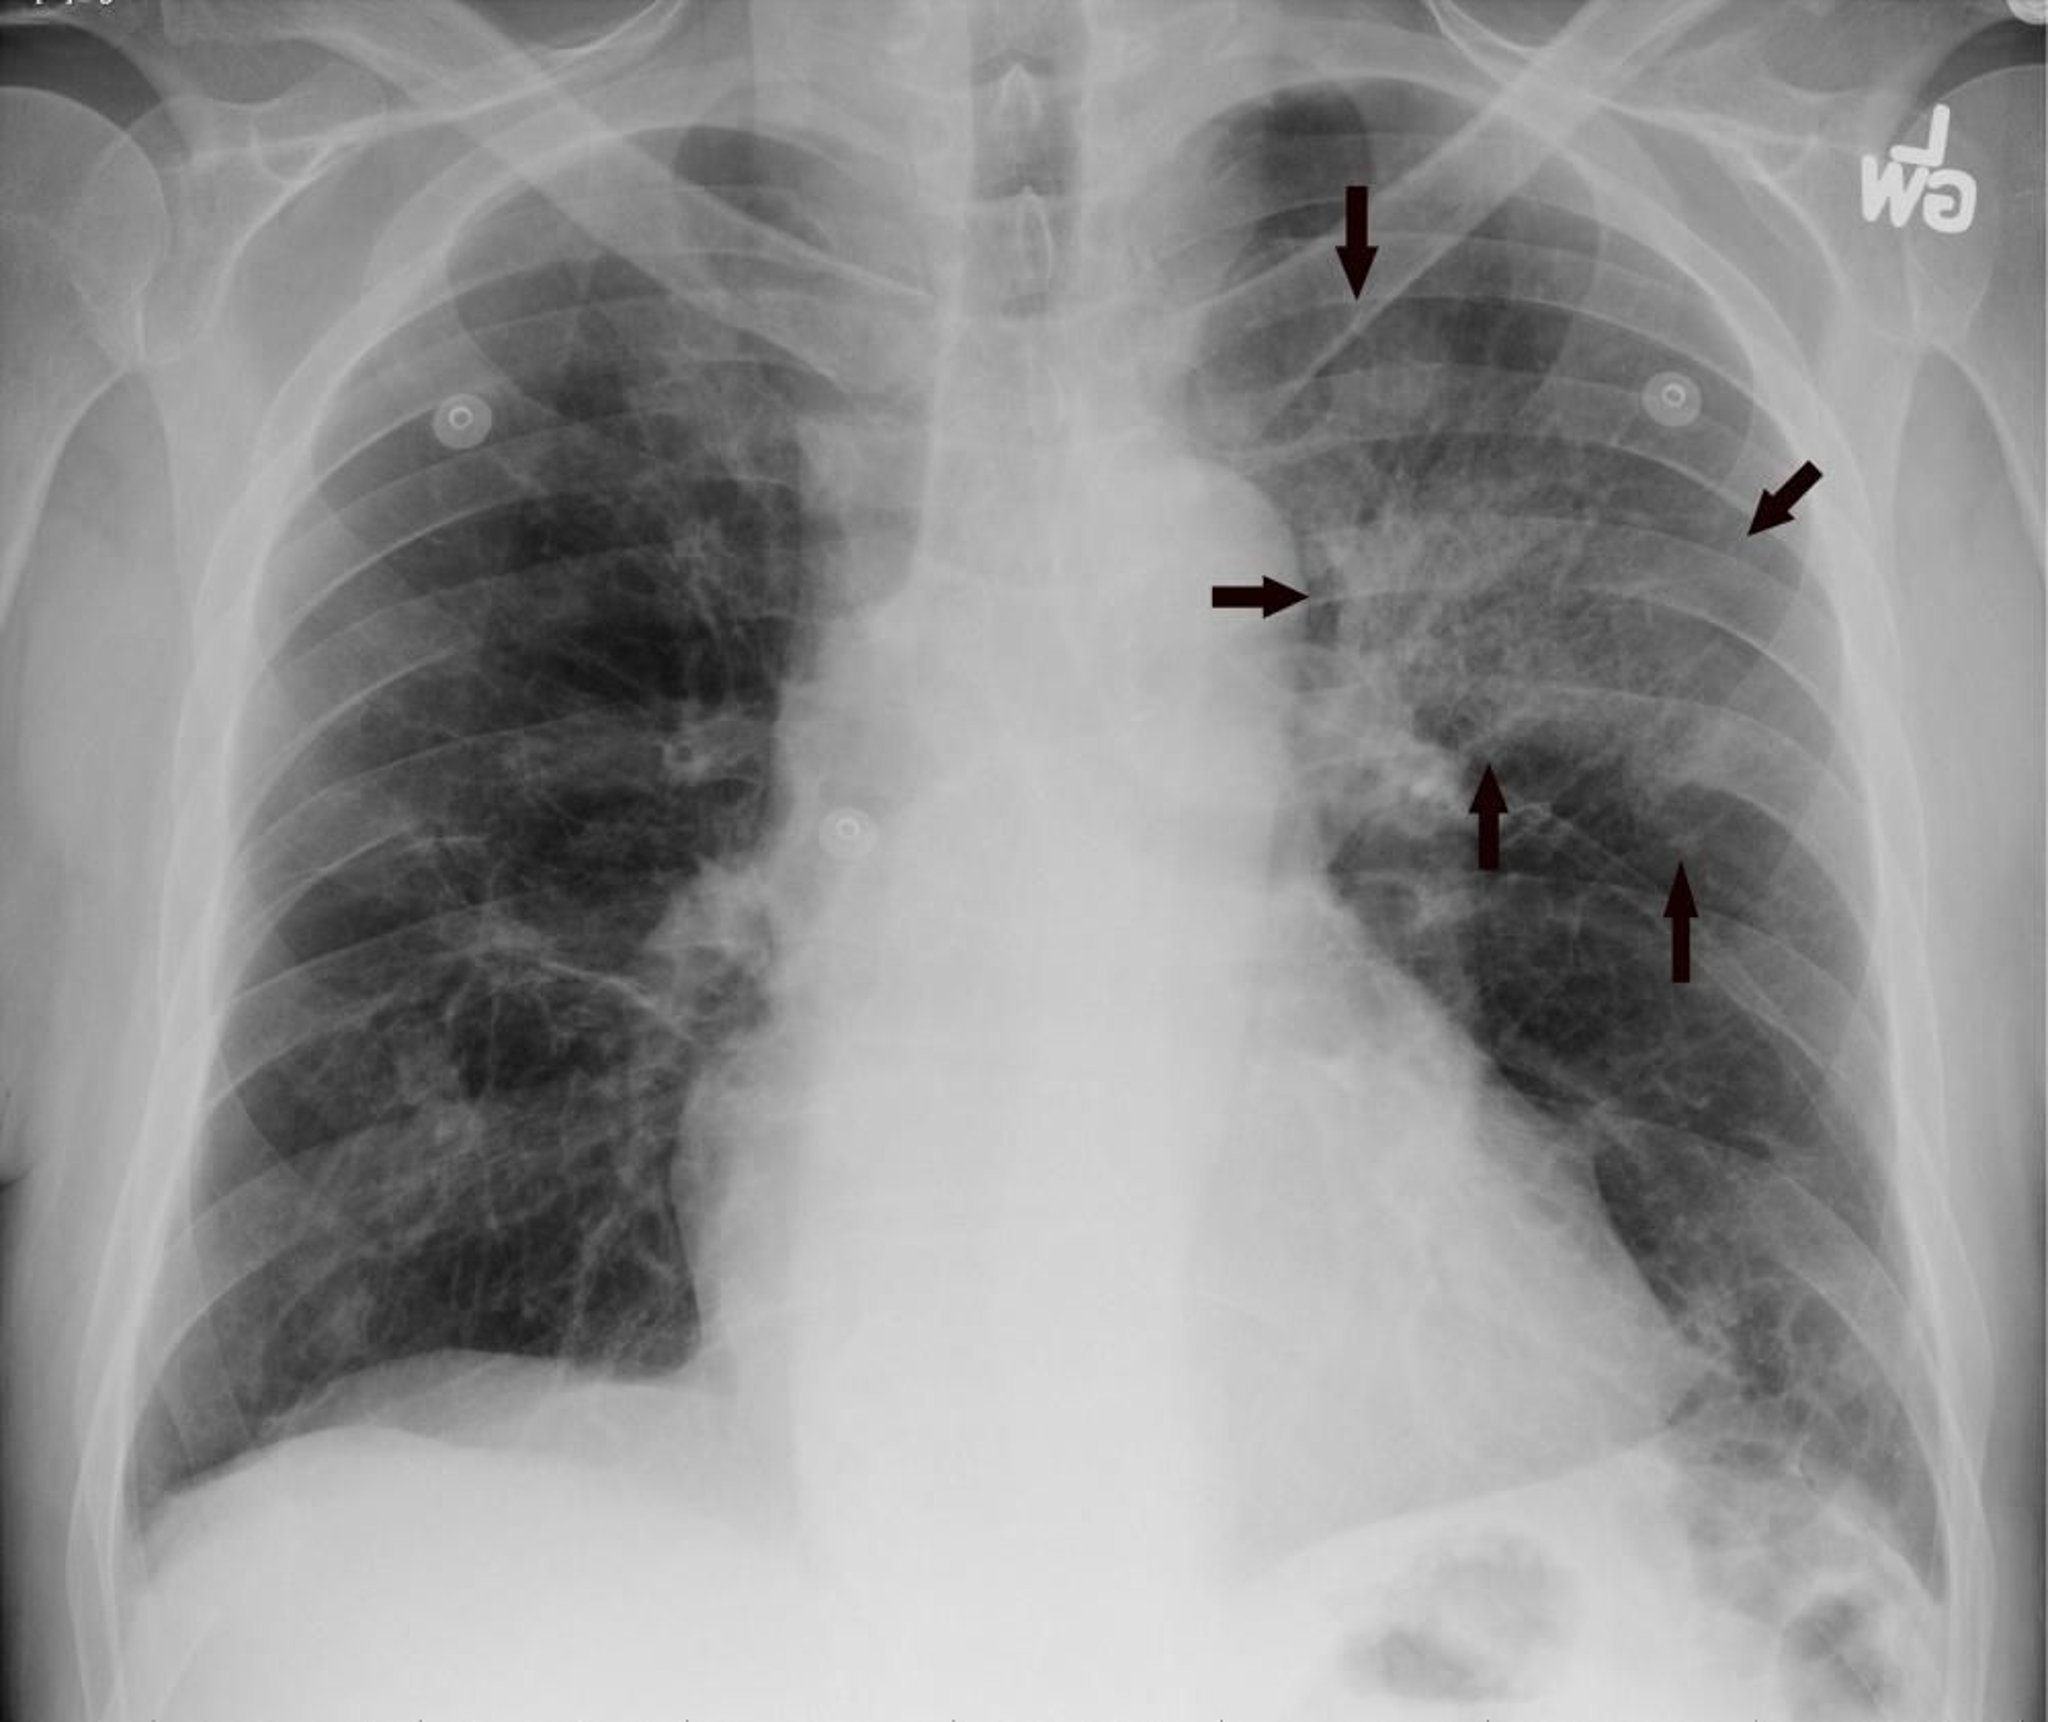

La RX postero-anteriore del torace mostra infiltrazione del lobo superiore sinistro compatibile con polmonite (frecce).